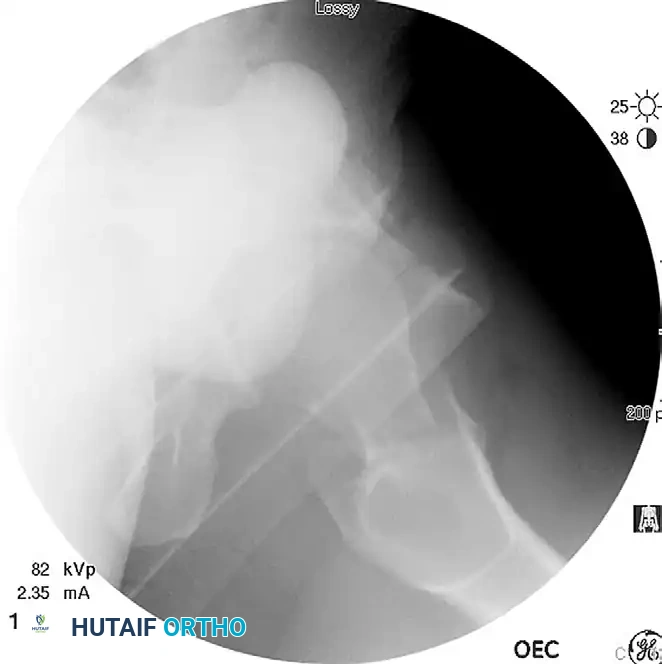

Displaced femoral neck fracture visualized prior to reduction.